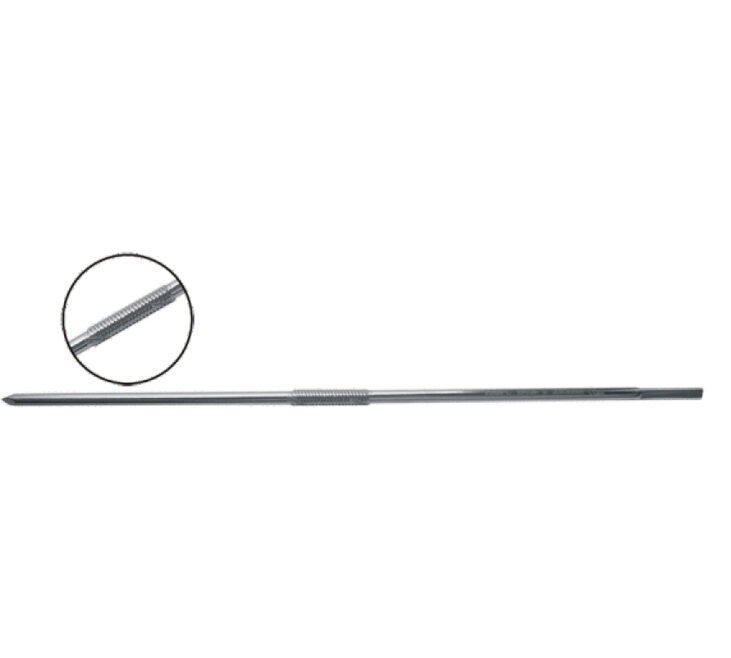

Denham Pin 9″ by KRENILA ORTHO is a high-strength orthopaedic traction pin designed for secure skeletal traction and temporary fixation. Manufactured from medical-grade stainless steel, it provides excellent strength, smooth insertion, and reliable performance. ISO certified and FDA approved.

The Denham Pin 9″ from KRENILA ORTHO is a precision-engineered orthopaedic implant used primarily for skeletal traction in trauma and fracture management procedures. Its robust design ensures strong anchorage in bone, providing reliable and stable traction during pre-operative and post-operative care.

Manufactured from medical-grade Stainless Steel, the Denham Pin offers high tensile strength, corrosion resistance, and excellent biocompatibility. The sharp trocar point allows smooth and controlled insertion with minimal bone and soft tissue trauma, while the threaded central portion ensures secure fixation.